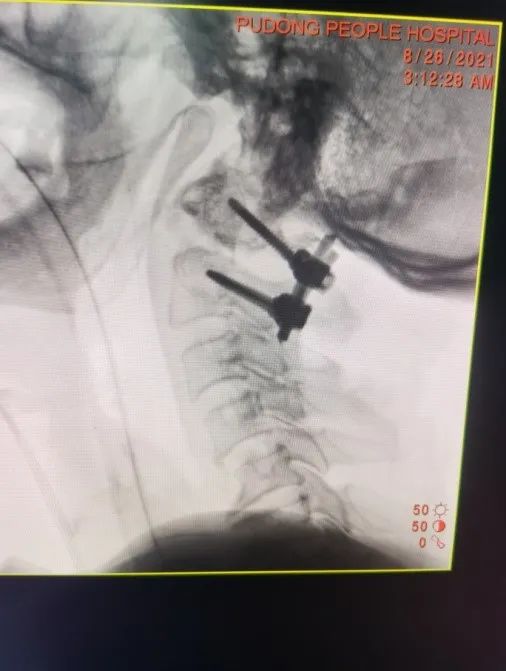

颈椎内植物X线片显示枢椎骨折端复位满意,寰枢椎脱位已复位

术后颈椎MRI显示C1-2椎管内容积恢复,颈椎生理弧度恢复满意。在伤后1周由骨科王健主任主刀为患者成功实施了C1-2椎弓根钉内固定手术。术中O-arm成像同步计算机数字导航技术确保了椎弓根螺钉植入的精确性,缜密的术前计划和娴熟的手术技术保证了手术的顺利实施。整个手术过程中患者生命体征平稳,术后即刻解除了繁重的颅骨牵引,使用方便拆装的颈托辅助外固定。目前患者正处于术后恢复期,病情平稳,并在康复医师专业指导下进行康复训练。